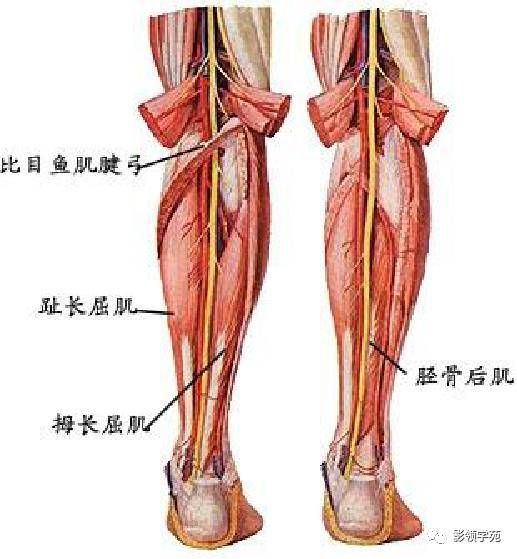

腹部动静脉

腹部动静脉